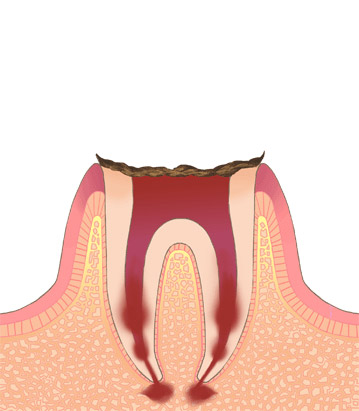

歯冠が溶けて無くなり、根の部分だけが残っている状態です。

やむを得ない場合は残った歯根部を抜歯します。抜歯した部分は傷が治った後に、ブリッジ・部分入れ歯・インプラントなどの方法で補うことになります。